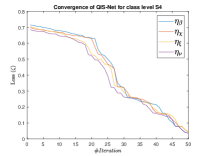

The suitable tailoring of the phase angle in the Hadamard gate advocates the stability of the QFS-Net or its convergence which is very crucial for self-supervised networks where the loss function (here error function) is dependent on the interconnection weights. Hence, the phase angles are evaluated using and as given in Equations 18 and 21, respectively. It is worth noting that the qutrit based quantum neural network provides faster convergence compared to the classical neural networks. This is due to the fact that whereas the classical neural networks are formed using the multiplication of input vector and the weight vector guided by an activation function, the quantum-based networks incorporate the frequency components of the weights and their inputs thereby enabling faster convergence of the network states. This inherent novel feature of the quantum neural networks facilitates the qutrit based fully self-organized quantum algorithm to be employed in QFS-Net to converge super-linearly, as shown in Figure 3. The loss function cum QFS-Net network error function is defined on quantum measurement in the following way.

| (37) |

where, represents the true interconnection weight terms of the inter-connection weights as expressed using the Hadamard gate () at an instance (). is a coherent error function of and . Convergence analysis of the proposed qutrit-inspired QFS-Net is provided in Appendix Section -A and demonstrated experimentally with qubit embedded QIS-Net [39] as shown in Figure 3. It can be summarized that the convergence of the QFS-Net is faster than that of the QIS-Net and also follows super-linearity. This claim is also substantiated by the number of iterations required to converge for each image slice in QFS-Net and QIS-Net as illustrated in Figure 4.